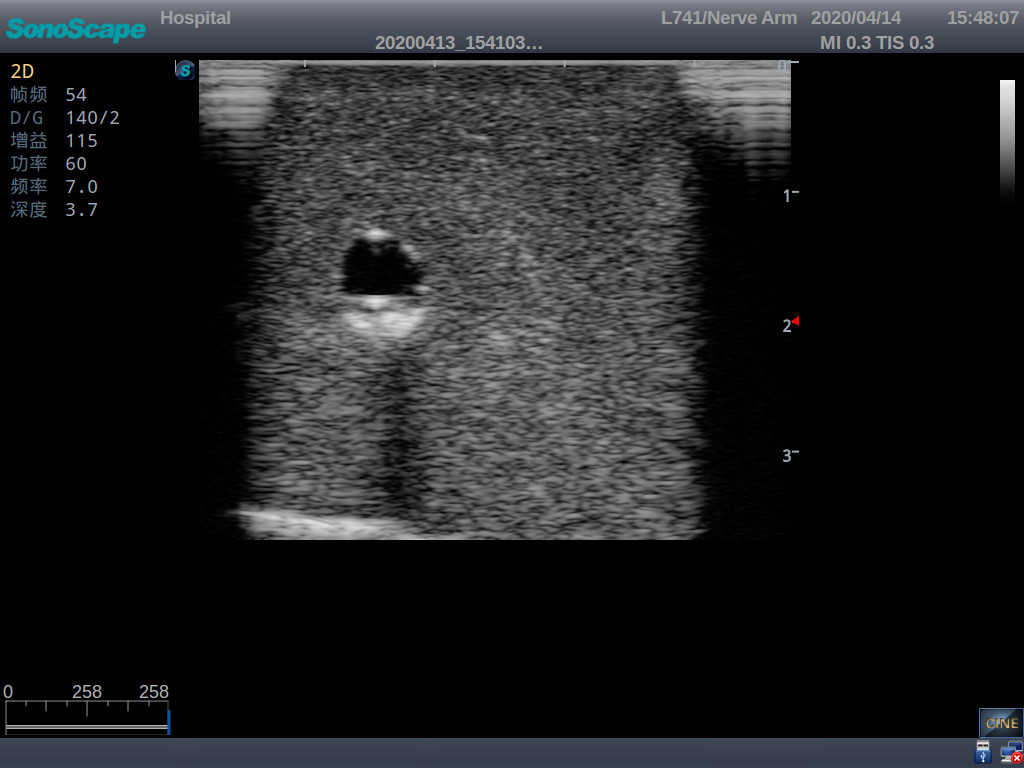

2) It can be used by real ultrasound machines

3) Clear and real images of the tissues and organs (basilic vein and superior vena cava)

4) When conducting vascular puncture, the piercing can be truly felt, and venous blood outflow can be seen

5) Observe the guide wire marches

6) Detect whether the catheter is properly placed